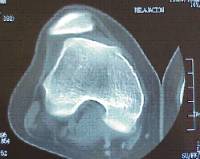

Es una alteración congénita que afecta a la morfología y a la estructura del menisco siendo más frecuente a nivel externo.

Presente entre el1 y el 5% de la población, la sintomatología clínica es muy variada dependiendo de la extensión del mismo (completo / incompleto) así como del mantenimiento de sus inserciones cápsulares.

El tratamiento es la meniscectomía parcial artroscópica y la sutura en casos de desinserción.

En pacientes asintomáticos se ha indicado el tratamiento quirúrgico preventivo debido a que puede condicionar un hipocrecimiento del cóndilo femoral y por tratarse de un menisco estructuralmente anormal con mayor susceptibilidad para sufrir lesiones.